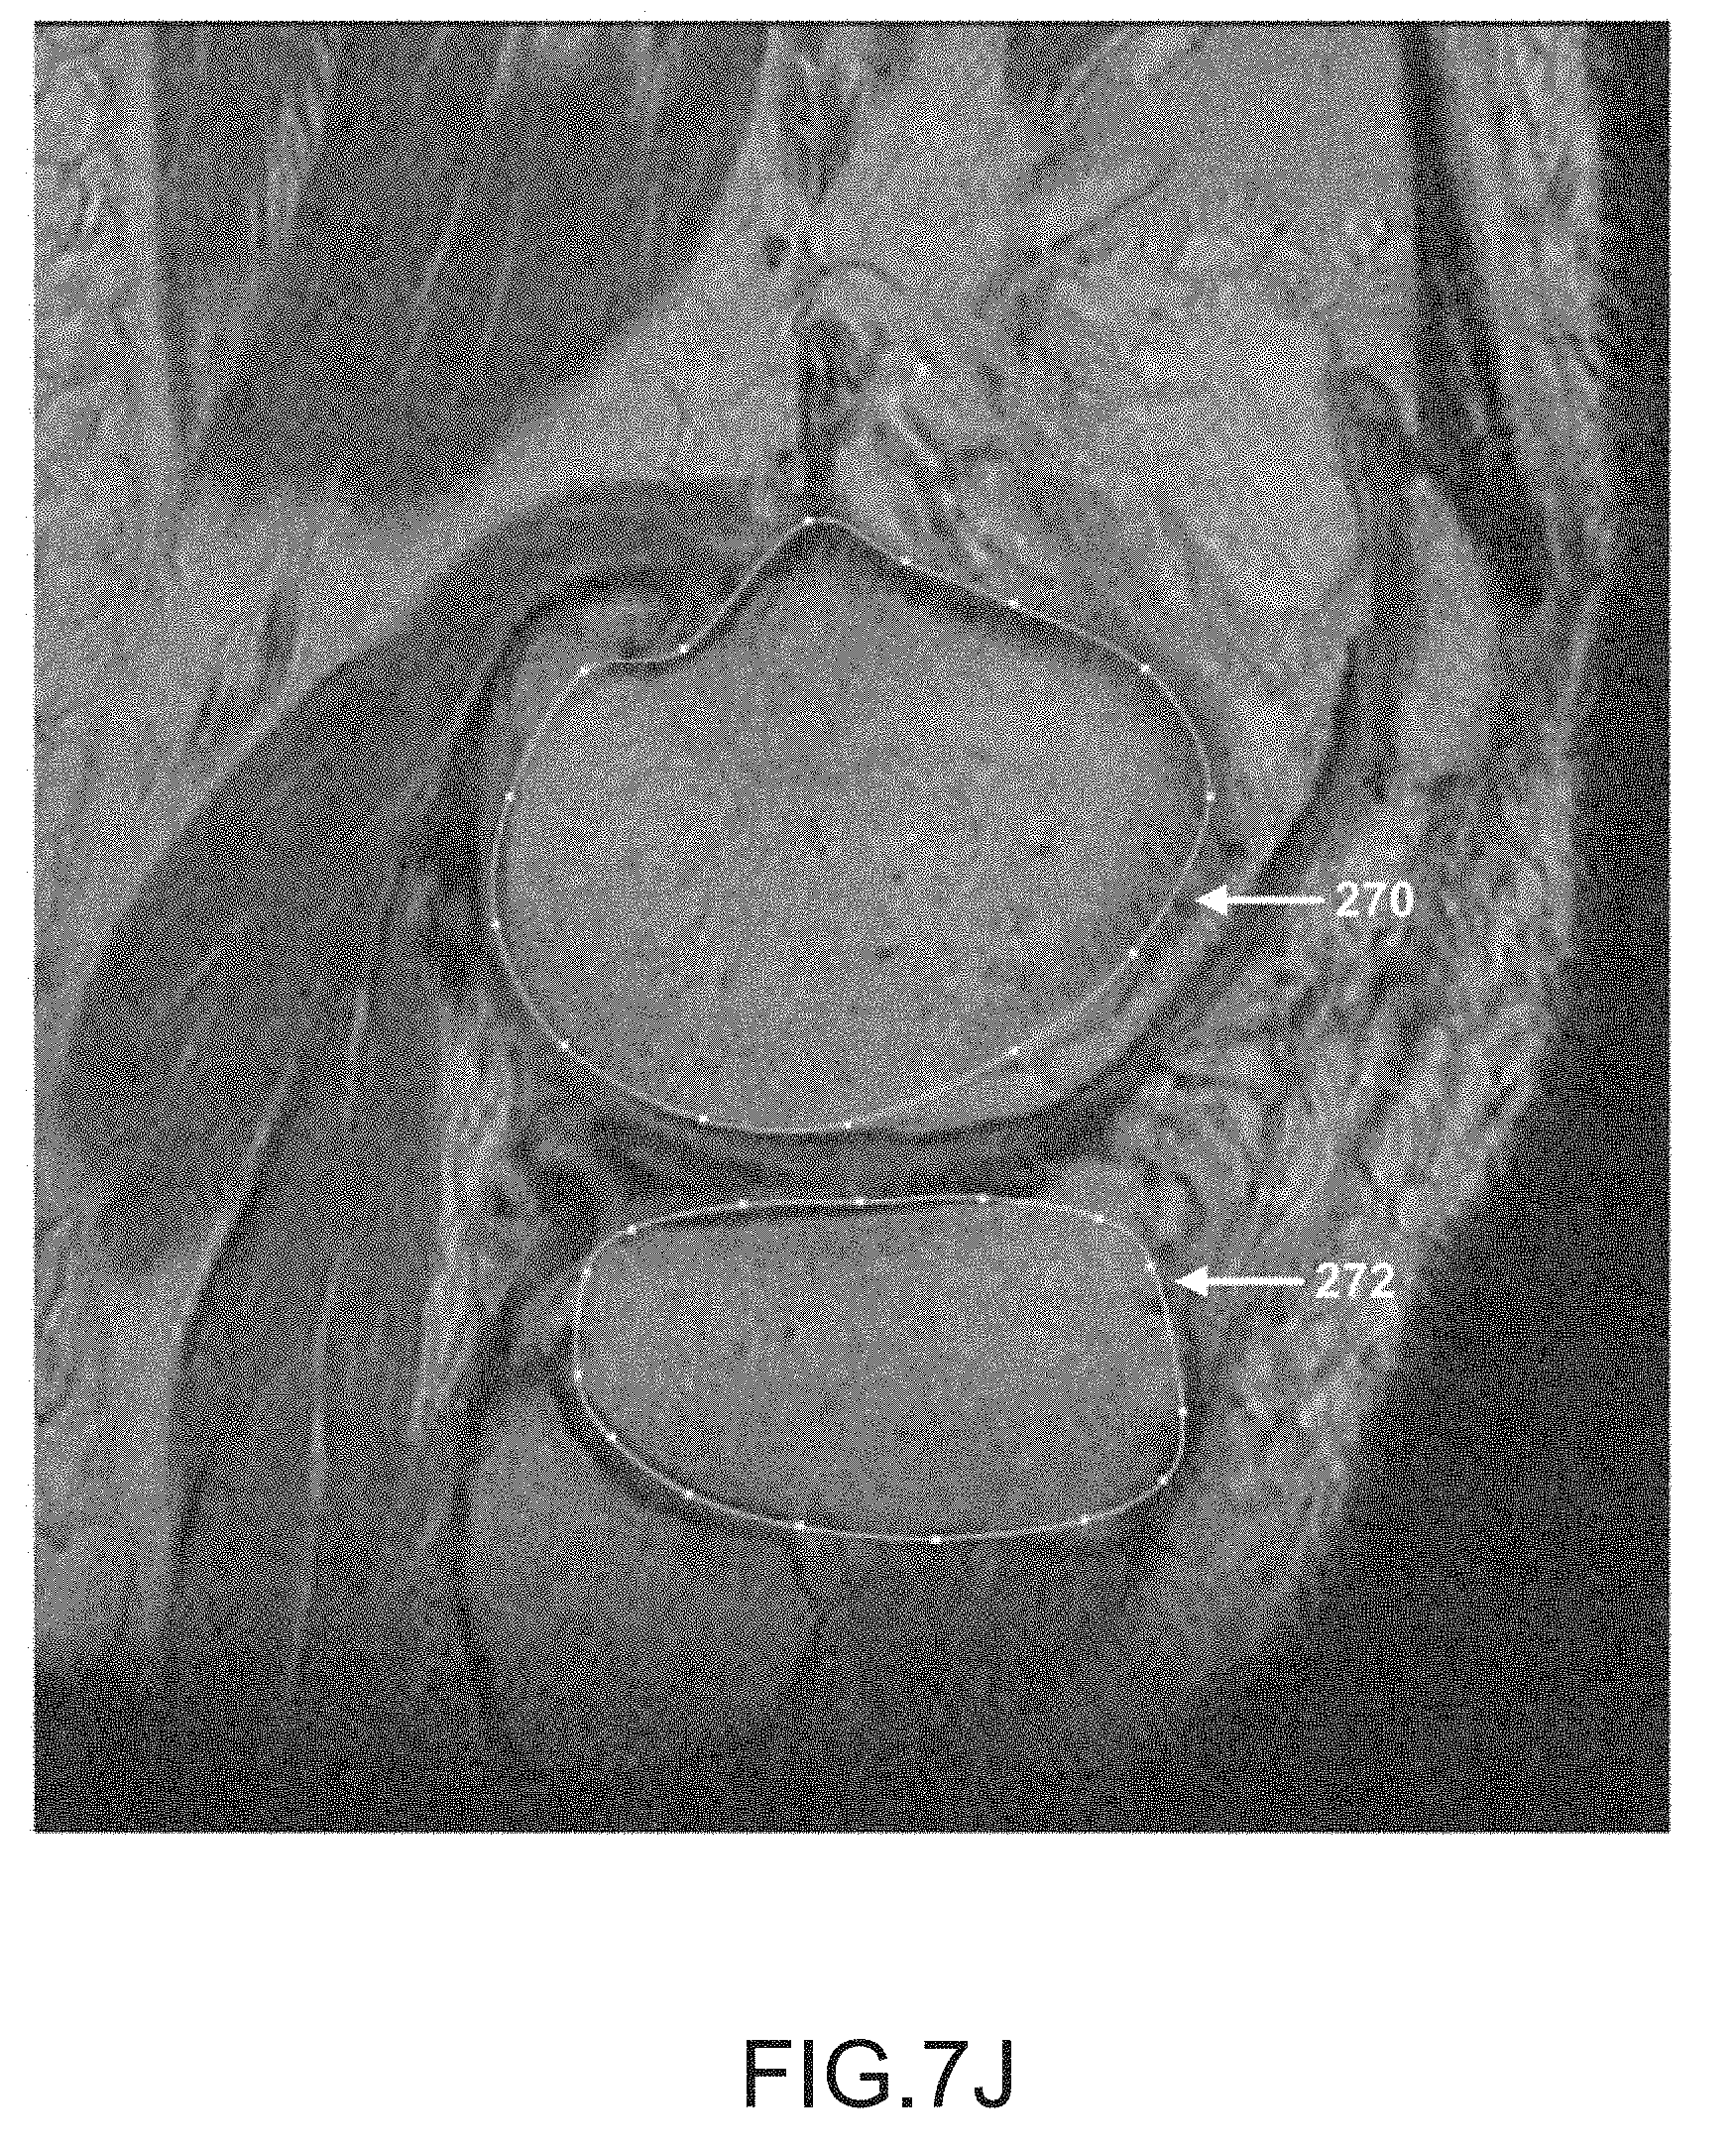

FIG. 7J is another sagittal plane image slice of a segmented femur and tibia.

[0060]

[0165]

After operation 256, operation 258 may be performed to segment the tibia data in the scan data. During this operation, the tibia is located and spline curves may be generated to locate and outline the shape of the tibia found in the scan slices, as depicted by tibia spline curves 272 in FIGS. 7A-7K. It should be appreciated that one or more spline curves may be generated in each slice to outline the tibia depending on the shape and curvature of the tibia as well as the tibia orientation relative to the slice direction.

Once the technician is satisfied with all of the tibia spline curves in the scan slices, operation 262 generates a watertight triangular mesh geometry from the tibia segmentation. The mesh closely follows the spline curves and smoothly interpolates between them to generate a 3D surface model of the tibia. FIG. 10 depicts a typical 3D mesh geometry 292 of a target tibia generated by one embodiment. Such a 3D model may be a 3D surface model or 3D volume model resulting from open-loop contour lines or closed loop contour lines, respectively. In one embodiment, such a 3D model as depicted in FIG. 10 may be a bone model 22 or an arthritic model 36.